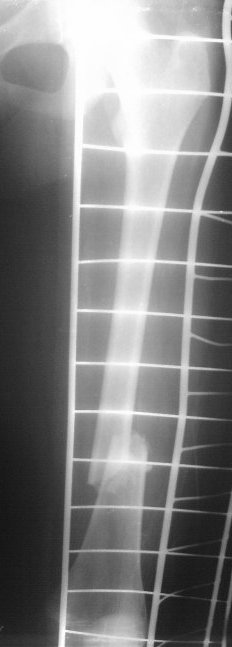

На сегодняшний день вот такая картина: девочка, 13 лет, 3 недели на скелетном вытяжении по поводу оскольчатого перелома нижней трети левого бедра.

Сейчас инфекцию "победили", отек бедра за последние дни значительно спал, но имеется укорочение 2 см, отломки уже "прихватились",

патологической подвижности нет.

Имя     : femur_lat.jpg